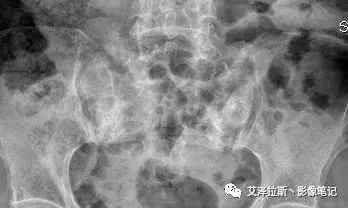

病例1:患者,女性,88岁,重度骨质疏松。

X线:

X线、CT:骶骨重度骨质疏松,双侧骶骨翼皮质断裂,分别见迂曲走行的纵行透亮线位于骶孔外侧,大致与骶髂关节间隙平行,骨折端局部可见骨痂、骨质硬化。

骶骨功能不全骨折

①单侧或者双侧骶骨翼骨折,典型者呈“H”形,即“Honda征”;

②骨折线位于骶孔外侧(如下图,主要发生于1区),通常可能会伴随耻骨的功能不全骨折(如:病例2 右侧耻骨上支骨折,L5双侧横突骨折);

③愈合期骨折线模糊,骨痂形成,骨质硬化;